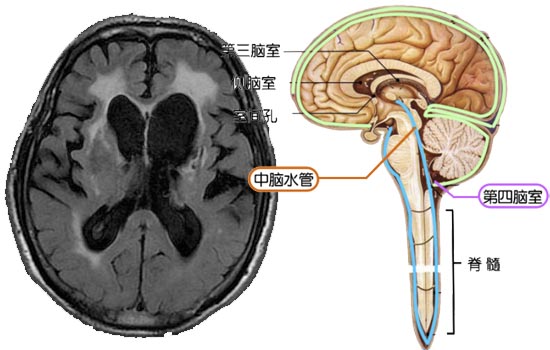

孩子在外地工作,除了过年过节,一般很少回来。为了健康起见,老伴催促他早晨起来去公园活动,老伴陪着去了几次,自己也去了几次,开始感觉不错,近来发现散步脚有些发飘,站不稳、踏不实,平时说话很少,然而近几个月变得沉默寡言,说话更少了,甚至很多时候不跟邻居打招呼。走起路来步履蹒跚,而且症状越来越严重,经常散步跌倒,有时老伴不得不搀扶着,还经常尿裤子,走路变得困难。老伴担心患者得了老年痴呆,找邻居开车送到较近的航空总医院就医,神经内科CT检查发现脑积水转入神经外科,肖庆主任经检查诊断为老年性正常颅压脑积水,病因为导水管狭窄引起脑脊液循环不畅。由于时间较长,脑中已出现较大量脑积水形成。肖庆主任经过术前评估、制订方案、术前准备,应用软性神经内镜入脑室疏通导水管,并吸出过量脑脊液,术后不久患者症状缓解,经过一段时间休养,基本恢复到一年前的状态。

近年来,随着人口老龄化加剧,老年脑积水患者数量不断增加,而且有年轻化趋势。资料显示,正常颅压脑积水引起痴呆的患者人数约占老年痴呆患病人数的20%,这些病人早期治疗预后良好,而且越早治疗脑组织的损伤越小,患者恢复的效果越好。如果不进行治疗任其发展,老年脑积水引起病理改变,表现为脑室系统逐渐扩大,第三脑室向下方隆起压迫垂体及视神经交叉部,透明隔可穿破,脑实质变薄,以额叶处最明显,甚至穿破侧脑室与蛛网膜下腔相通。使得脑中胼胝体、锥体束、基底节、四叠体、脉络丛及脑干等处均可因长期受压而萎缩,导致白质脱髓鞘变、神经轴受压变形、胶质增生及神经细胞退行性变等,进而出现一系列脑积水综合征,危害很大。因此,当老人出现记忆力减退、运动障碍、大小便失禁等症状时,要及时到医院进行相关检查,以免延误病情。